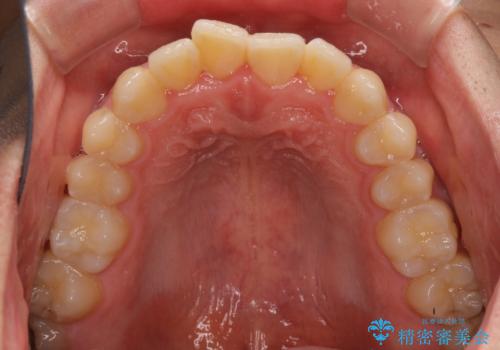

- 上下前歯のデコボコを気にして来院された患者様です。

叢生は軽微であり、費用を抑えて期間もあまりかけずに治療をしたいとのことで、インビザライン・ライトを用いて矯正治療を行うこととしました。